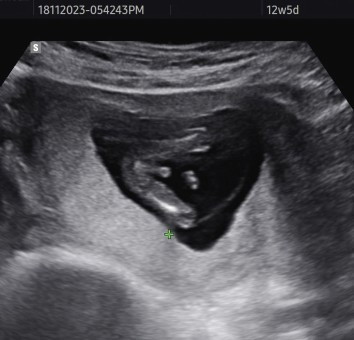

Sy baru buat NT scan (12w5d) kat Sonobee. Harini banyak file gmbr n video sy dpt. Salah satunya gmbr ni, ni gmbr gender ke? Sbb masa scan sonographer tk ckp psl gender pun n sy pun tk tanya sbb trlalu awal. Alhamdulillah anak sihat sbb cecair kt tengkuk kurang dari 3mm. #firstmom #ingintahu #pleasehelp #seriusnanya #bantusharing #ntscan